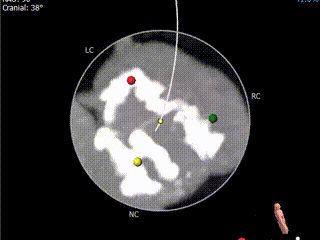

术前CT评估:

主动脉根部评估:

冠脉评估:

钙化评估:

重度钙化,左冠窦钙化延伸至LVOT水平